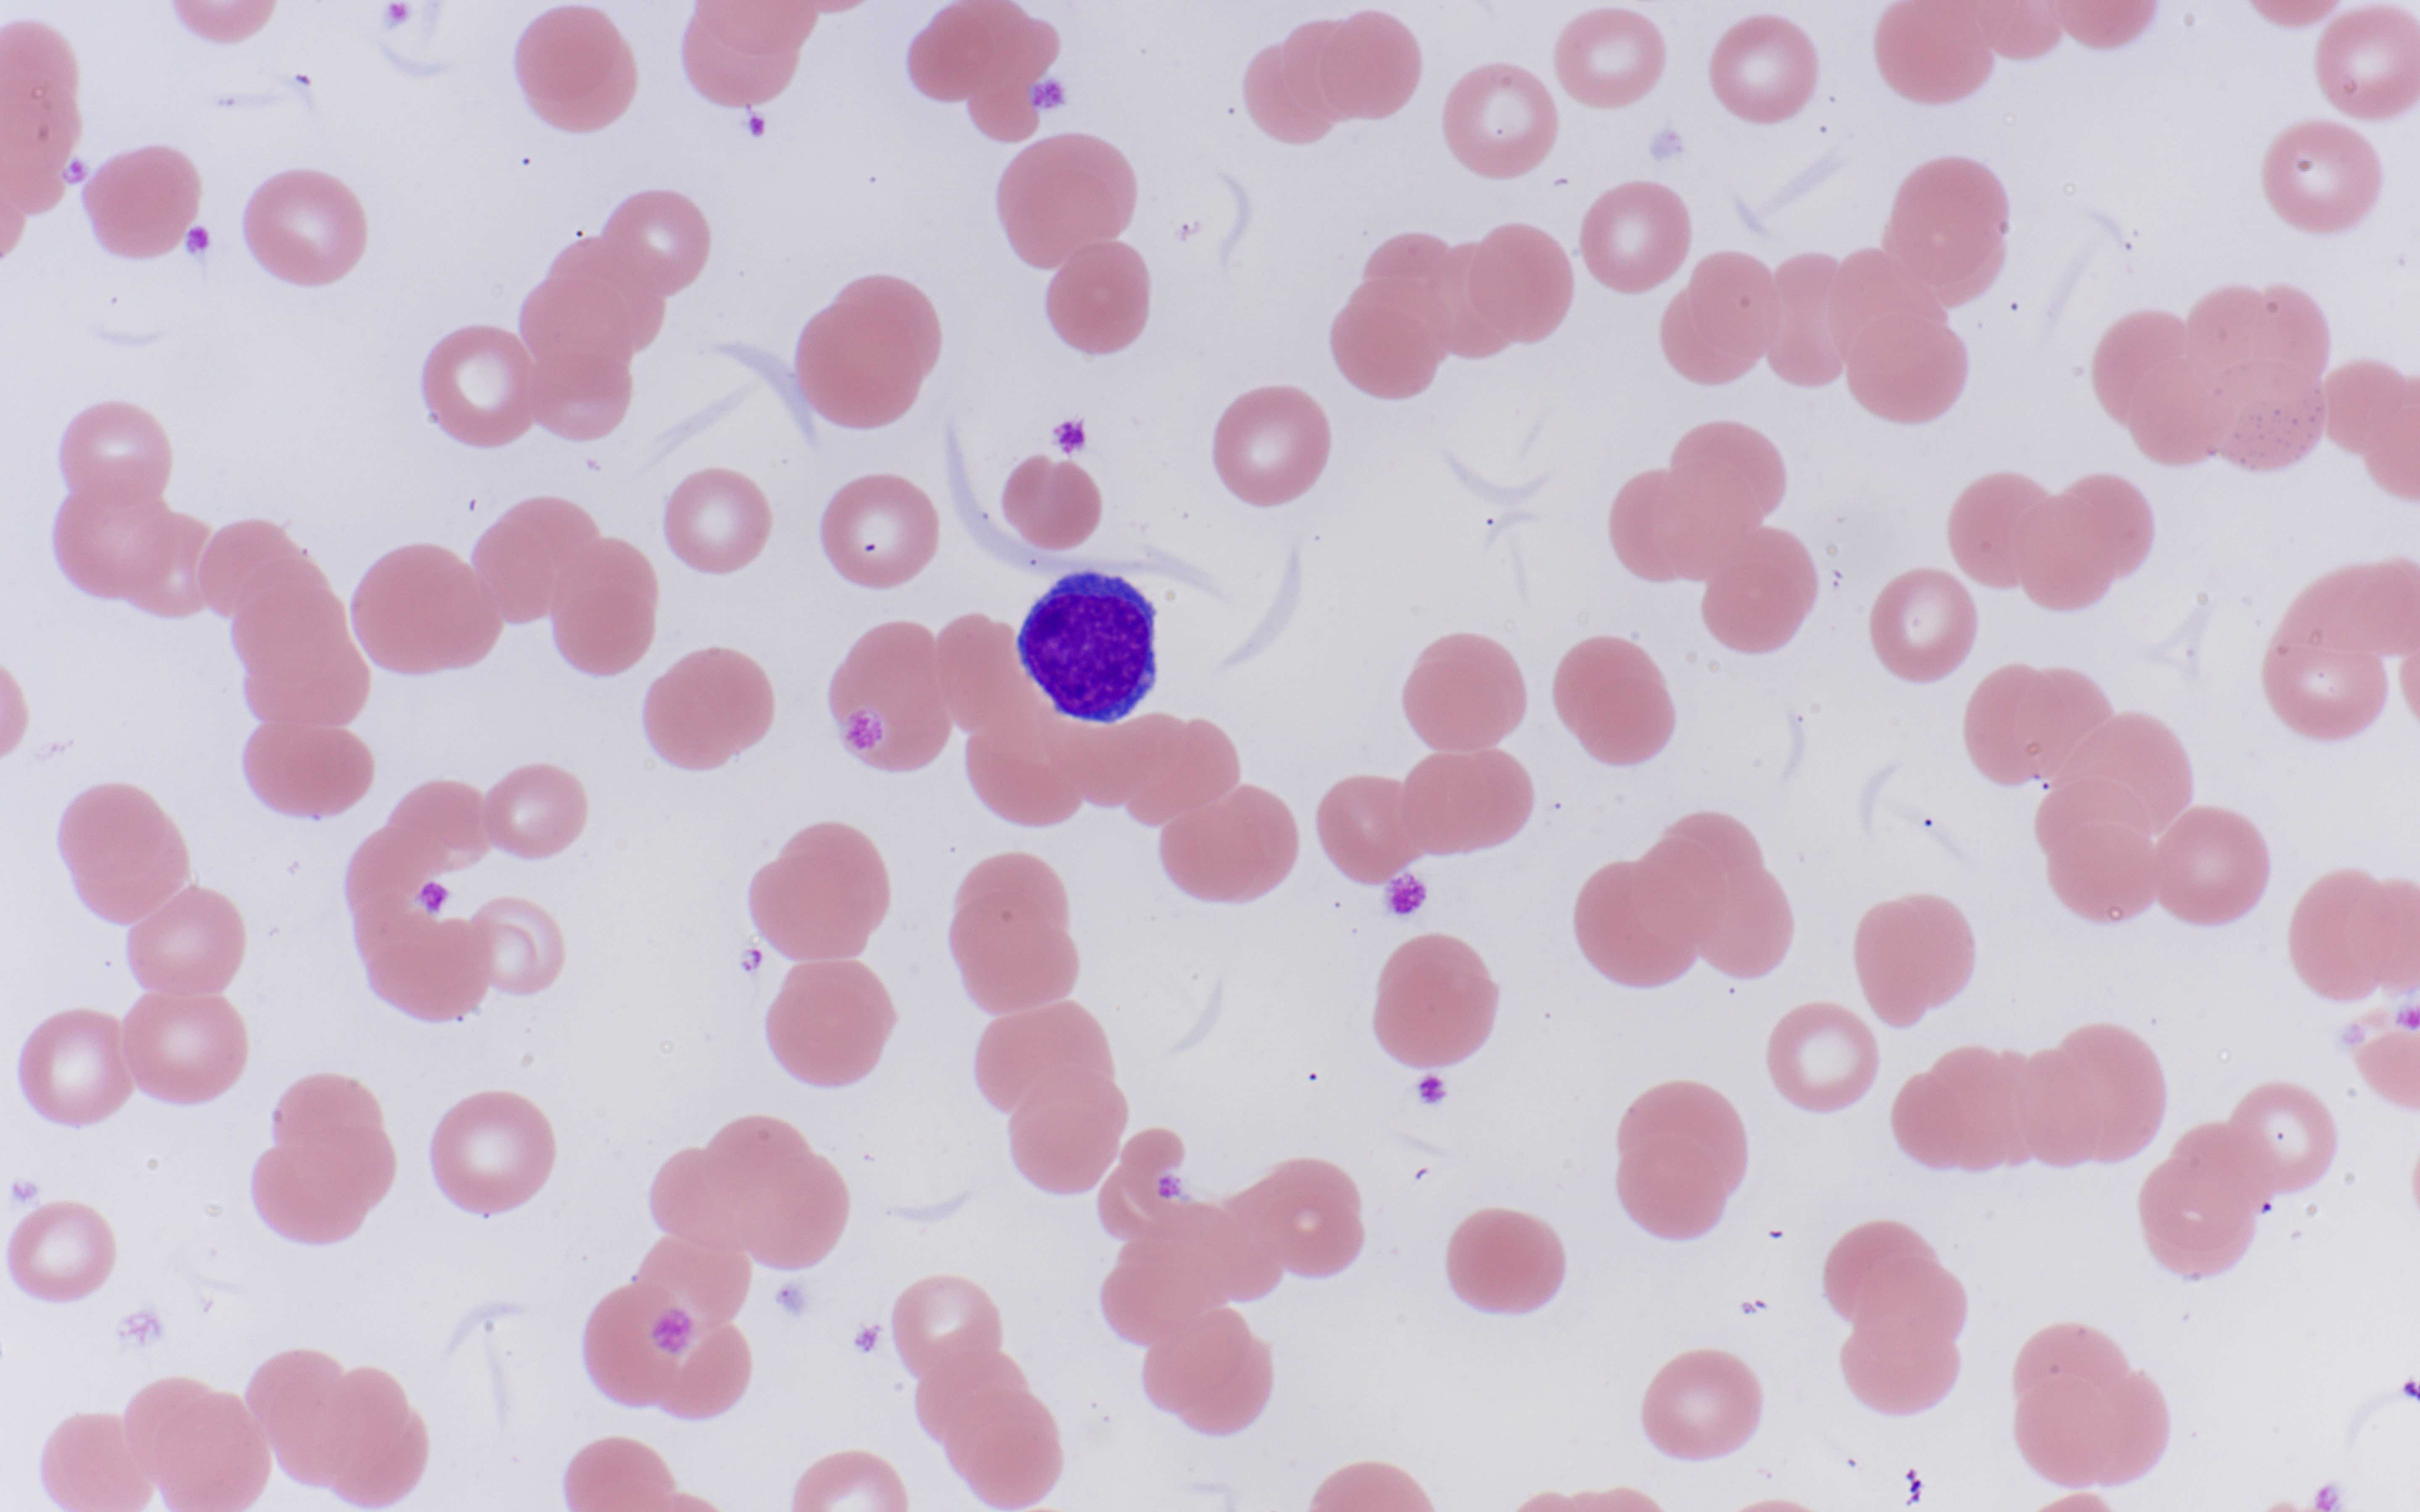

Peripheral smear description

- Rouleaux formation: erythrocytes resemble stacked coins; related to quantity and type of M protein, not specific and may be caused by alterations in other plasma proteins (Biophys J 2000;78:2470, American Society of Hematology: Rouleaux Formation [Accessed 26 May 2022])

- Leukoerythroblastic reaction can occur with extensive marrow involvement

- Circulating plasma cells can be seen in ~15% of cases, usually small numbers not meeting criteria for plasma cell leukemia (> 2 x 109/L or 20% of the leukocyte count)